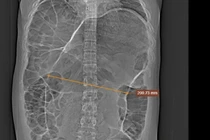

ngo-doc-ruou-tai-bv-thong-nhat.jpg

Một ca ngộ độc rượu đã được điều trị tại Bệnh viện Thống Nhất TPHCM.